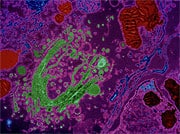

A novel carotenoid can do something scientists had long thought was impossible—trigger the burning (or thermogenesis) of white body fat—without producing stimulatory effects. In addition to inducing significant weight loss in human study subjects, this plant extract has been shown to improve blood markers associated with vascular and inflammatory disorders. Why is burning white body fat so critical? Because new studies show there is a significant decrease in resting energy expenditure as humans age. If you’ve ever wondered why diet and exercise so often fails to produce meaningful weight loss, scientific research shows that with normal aging, metabolism slows significantly, while white body fat mass increases. Up until now, people seeking to boost their resting metabolic rate had to rely on compounds that produced unpleasant stimulating effects. That has all changed with the discovery of a new carotenoid that safely increases resting energy expenditure at the cellular level—with none of the side effects associated with high-dose ephedra. In this article, we look at the recent studies that document the impressive ability of this carotenoid to reduce body fat while simultaneously providing a range of life-saving health benefits. Fucoxanthin: The New CarotenoidHuman health is highly reliant on the ingestion of plant carotenoids. For example, inadequate intake of the carotenoids lutein and zeaxanthin can result in the development of macular degeneration—the leading cause of blindness in the elderly. Fucoxanthin is a carotenoid derived from a special seaweed that has been extensively studied for its antioxidant powers.1-3 Animal studies have demonstrated its beneficial effects in stroke prevention,4 reduction of inflammation,5 and slowing the growth of various cancer cell types.6-10 Based on this information alone, fucoxanthin would be an effective nutritional supplement to add to one’s daily program. It is the favorable effect on cell energy expenditure, however, that gives fuco-xanthin its remarkable fat-reducing properties. Fucoxanthin facilitates youthful energy meta-bolism by activating a special cellular protein called mitochondrial uncoupling protein 1 (or UCP1). As you will soon read, mitochondrial uncoupling protein 1 promotes the natural removal (metabolic burning) of white fat stored in the body. A Serendipitous FindingA group of Japanese marine biologists11 discovered during their research that when study animals were supplemented with fucoxanthin, something unexpected occurred—mitochondrial uncoupling protein 1 (UCP1) was expressed in white adipose (fat) tissue. This unique protein (UCP1) is normally only active in brown fat, a type of fat that is capable of non-shivering thermogenesis, a process that ultimately results in an increase in metabolic rate by “uncoupling” energy transfer in the cells. White fat, on the other hand, often accumulates excessively in human bodies as we age, and white fat generally does not express UCP1 to any appreciable degree. What this means is that fucoxanthin can help white adipose tissue mimic some of the thermogenic properties of brown fat, ultimately resulting in a safe increase in metabolic rate and enhanced fat-burning.

In the experiment, these scientists fed fuco-xanthin-rich extracts from edible seaweed to rats and mice and then measured the weight of white adipose tissue in the animals’ abdomens. A diet containing the same calorie content was fed to a second set of animals that served as the control group. In the fat tissue of the animals who were given fucoxanthin, the scientists found noticeable increases in the expression of the fat-burning protein UCP1. In the control animals who did not receive fucoxanthin, little UCP1 expression occurred in their fat. The fucoxanthin-supplemented animals demonstrated significant loss of white adipose tissue weight, whereas there was no weight loss at all in animals fed the control diet.11 The same researchers then turned their attention to the effects of fucoxanthin and its derivatives on fat cell formation in cultured cells. Treatment of pre-adipocytes (cells that will eventually become fat cells) with fucoxanthin prevented lipid (fat) accumulation inside the developing cells. It was also converted by the cells into a compound, fucoxanthinol, which prevented the cells from “growing up” into mature fat cells.12 In essence, fucoxanthin stopped fat in its tracks. Evidence that fucoxanthin reduces the growth of new blood vessels in adipose tissue suggests that this may be another mechanism by which the seaweed derivative blocks development of new fat stores.13 Reduced Blood Sugar Levels

These prolific researchers then examined the combination of fucoxanthin and fish oil on white adipose (fat) tissue weight and blood glucose in obese mice with type 2 diabetes.14 Mice were supplemented for four weeks with fucoxanthin alone, fucoxanthin plus fish oil, or a control diet with the same calorie content. Fucoxanthin alone markedly reduced gain in white fat tissue weight compared with controls, while the animals given fucoxanthin and fish oil had still further reductions in weight gain. Groups receiving either fucoxanthin alone or fucoxanthin plus fish oil experienced significant reductions in blood glucose and plasma insulin concentrations, as well as in inflammatory markers such as TNF-alpha—all highly beneficial effects in this animal model of the human metabolic syndrome (which is so often characterized outwardly as abdominal obesity)! Altering The Fat-Making ProcessThe exact mechanism by which fucoxanthin reduces body fat is still undergoing scientific evaluation, but we know that it has to do with the process by which the body normally transfers and stores energy, known as “coupling.”11

Under normal circumstances, chemical energy from food is poured into molecules of adenosine triphosphate (ATP), which are then used by cells for energy.15 Any unused energy from the ATP molecules is stored for future use through the formation of new fat molecules. This is why people who consume more calories than they expend end up gaining weight in the form of fat. Then, when the body’s caloric needs increase (say, with increased exercise), fat molecules are broken down and their stored energy is put back into new ATP molecules which provide it to working cells. Scientists refer to this entire process as “coupling,” which efficiently transforms chemical energy to physical energy and back again.15-17 Under normal circumstances, this process is highly efficient within the body. It is during this “fat-making process” that fuco-xanthin can have a beneficial influence on the mechanism that causes so many people to gain unhealthy weight in the form of fat. Fucoxanthin induces the production of a protein that “uncouples” cellular energy transfer so the body is less efficient at converting food energy into fat.18 In the human body, excess energy (calories) is stored in the form of white fat. An increase in metabolic rate can allow the burning of ingested calories and promote the removal of stored body fat. Interestingly, animals—especially those that hibernate—have a different kind of fat (brown fat) that enables them to keep warm without physical movement through the fat-burning process. This process was considered impossible for non-infant humans, because adult humans largely have white fat that was not previously believed to possess the same properties as brown fat. The remarkable “uncoupling” properties of fucoxanthin essentially allow white fat cells to mimic some of the properties of brown fat and increase resting energy expend-iture, therefore relying on the burning of stored body fat for fuel.